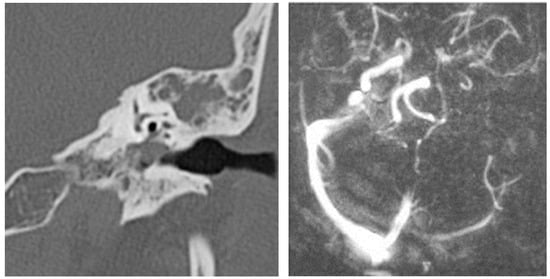

3.1.2. Computed Tomography and Magnetic Resonance Imaging

| CT Aspects | Number of Patients | Percentage |

|---|---|---|

| Fluid accumulation | 168 | 100% |

| Osteolysis | 152 | 90.47% |

| Osteocondensations | 128 | 76.19% |

| Cholesteatoma | 48 | 28.57% |

| Exocranial extensions | 48 | 28.57% |

| Intracranial extensions | 24 | 14.28% |

| Changes to the external auditory canal | 68 | 40.47% |

| Ossicular chain damage | 144 | 85.71% |

| MRI Aspects | Number of Patients | Percentage |

| Edema | 128 | 100% |

| Cholesteatoma | 40 | 31.25% |

| Exocranial extensions | 40 | 31.25% |

| Intracranial extensions | 32 | 25% |

| Inner ear damage | 20 | 15.62% |